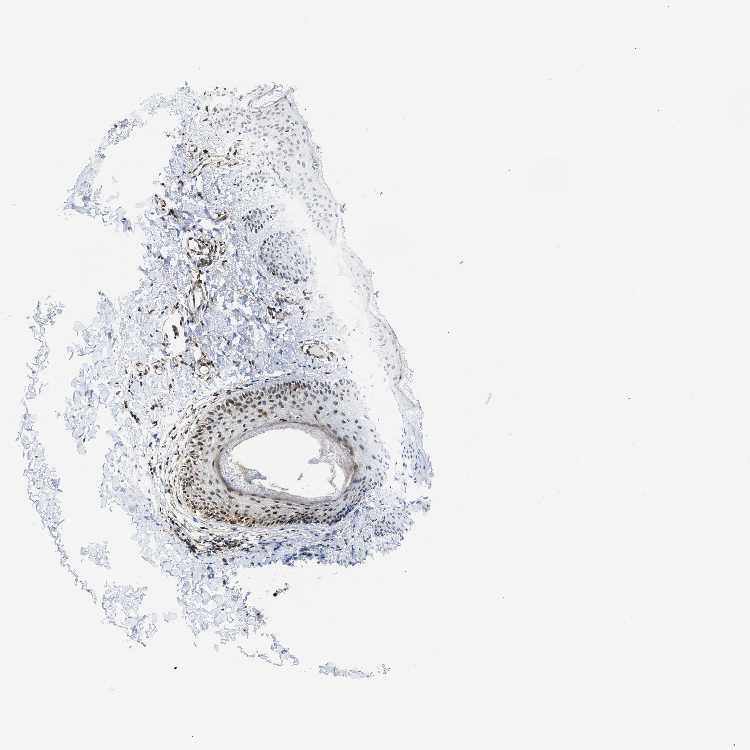

SKIN 1 - Antibody stainingi

Antibody staining in the annotated cell types in the current human tissue is reported as not detected, low, medium, or high, based on conventional immunohistochemistry profiling in selected tissues. This score is based on the combination of the staining intensity and fraction of stained cells. Each image is clickable and will lead to virtual microscopy that enables deeper exploration of all samples and also displays staining intensity scores, fraction scores and subcellular localization as well as patient and tissue information for each sample.

Antibody HPA015083Antibody CAB020840

Langerhans Not detectedNot detected

Fibroblasts LowLow

Keratinocytes Not detectedLow

Melanocytes MediumNot detected